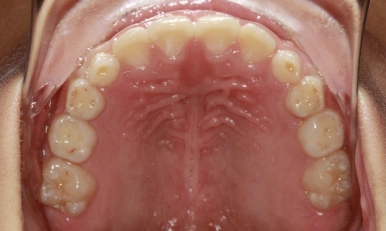

Patient Results